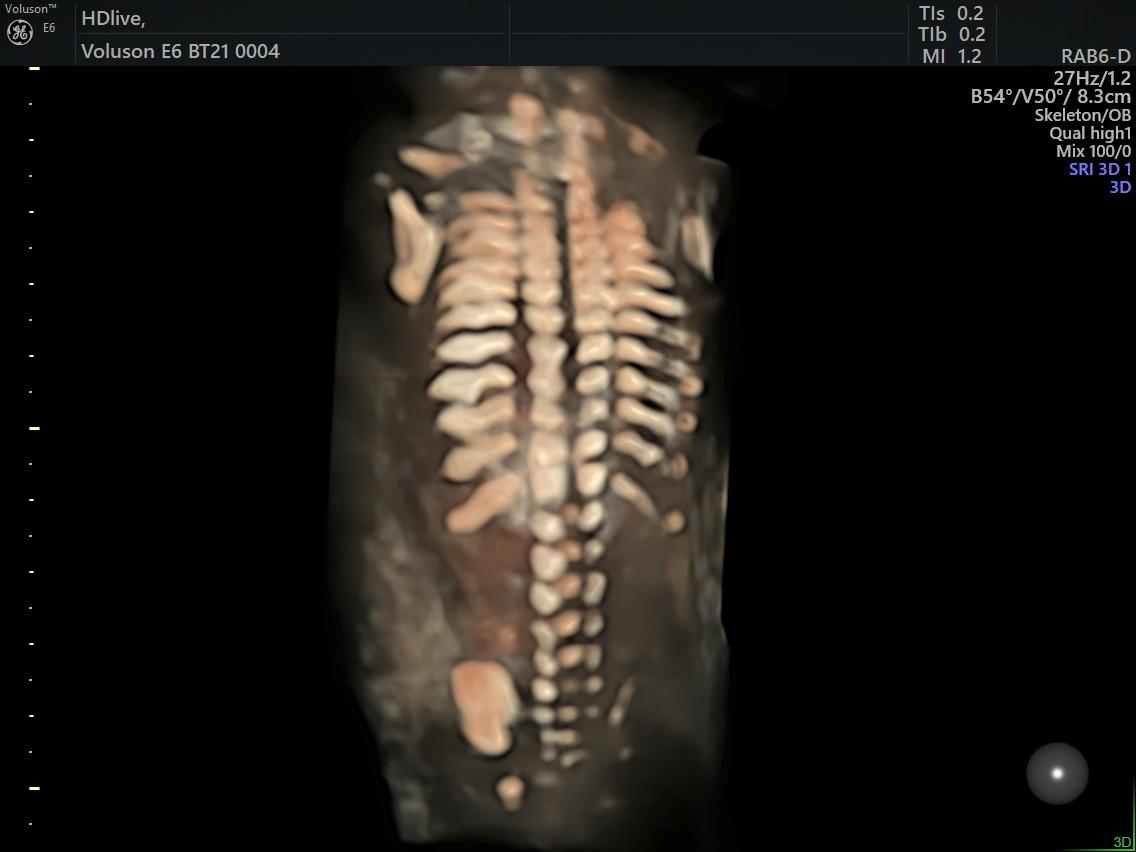

Fetal Medicine

Ultra Sound

Gallery

Images

Photos